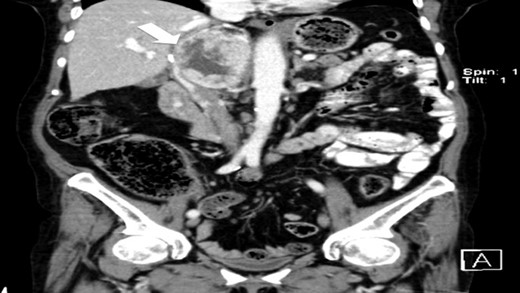

The authors report a case of a 64-year-old female, with no relevant family history and a past medical history of recently diagnosed supraventricular tachycardia, arterial hypertension, type 2 diabetes mellitus, euthyroid multinodular goiter and chronic venous insufficiency. She was referred to our Institution from other Hospital where she went due to paroxysms of palpitations, headache and diaphoresis, that led to biochemical investigation that was remarkable for: total plasmatic cathecolamines: 73 747 ng/L (normal range (NR) <598 ng/L), plasmatic noradrenaline: 73 589 ng/L (NR <420 ng/L), adrenaline: 130 ng/L (NR <84 ng/L), plasmatic dopamine: 28 ng/L (NR <94ng/L), aldosterone: 87,5 ng/dL (NR 4–31 ng/dL), plasmatic renin activity: 33 ng/mL/h (NR 0,5–4 ng/mL/h), Vanylmandelic acid: 39,2 mg/24 h (NR <13,6 mg/24 h). Abdominal contrast enhanced CT scan revealed a large (70 × 35×78 mm3), hyperdense (20 HU) right adrenal mass. Abdominal magnetic resonance (MRI) also described an adrenal mass with 66×33 mm2, suggestive of pheocromocitoma (slightly hypointense on T1 and markedly hyperintense on T2 weighted imaging). No vascular nor locoreginal lymph node involvement were found and the left adrenal was radiologically normal. The patient underwent genetic testing with next generation sequencing, that excluded mutations of the succinate dehydrogenase (SDHB, C, D and A), MEN2, VHL, Neurofibromatosis type 1 genes. Genetic testing for MAX and TMEM127 were not performed due to institutional unavailability. Pre-operative pharmacological therapy was initiated with phenoxybenzamine (10 mg twice a day), followed by bisoprolol (20 mg/day) and amlodipine (5 mg/day), which rendered the patient fit for surgery. The patient underwent transperitoneal laparoscopic right adrenalectomy. Intraoperatively, a hipervascularized right adrenal gland with adhesions to the upper pole of the kidney was identified and excised, with no complications recorded. In the immediate post-operative period, antihypertensive drugs were stopped and blood pressure remained normal until the second post-operative day, when hypertension and tachycardia recurred, leading to urinary metanephrine reevaluation on the 10th post-operative day. The results were highly suggestive of disease persistence (urinary normetanephrines >10 500 ng/L (NR <600 ng/L)). Histology revealed no signs of neoplasia. Abdominal CT scan revealed the persistence of a solid heterogeneous nodule, with 70 × 49 × 87 mm3 (AP × T × L) adjacent to upper right renal pole, with peripheral contrast enhancement and central necrosis (Figs 1–3). This findings suggested abdominal paraganglioma (of the organ of Zuckerkandl). Due to the higher malignant potential of paragangliomas, an 123I-MIBG scintigraphy was performed, excluding metastatic disease.

CT scan (coronal) of the heterogenous solid nodule (white arrow).